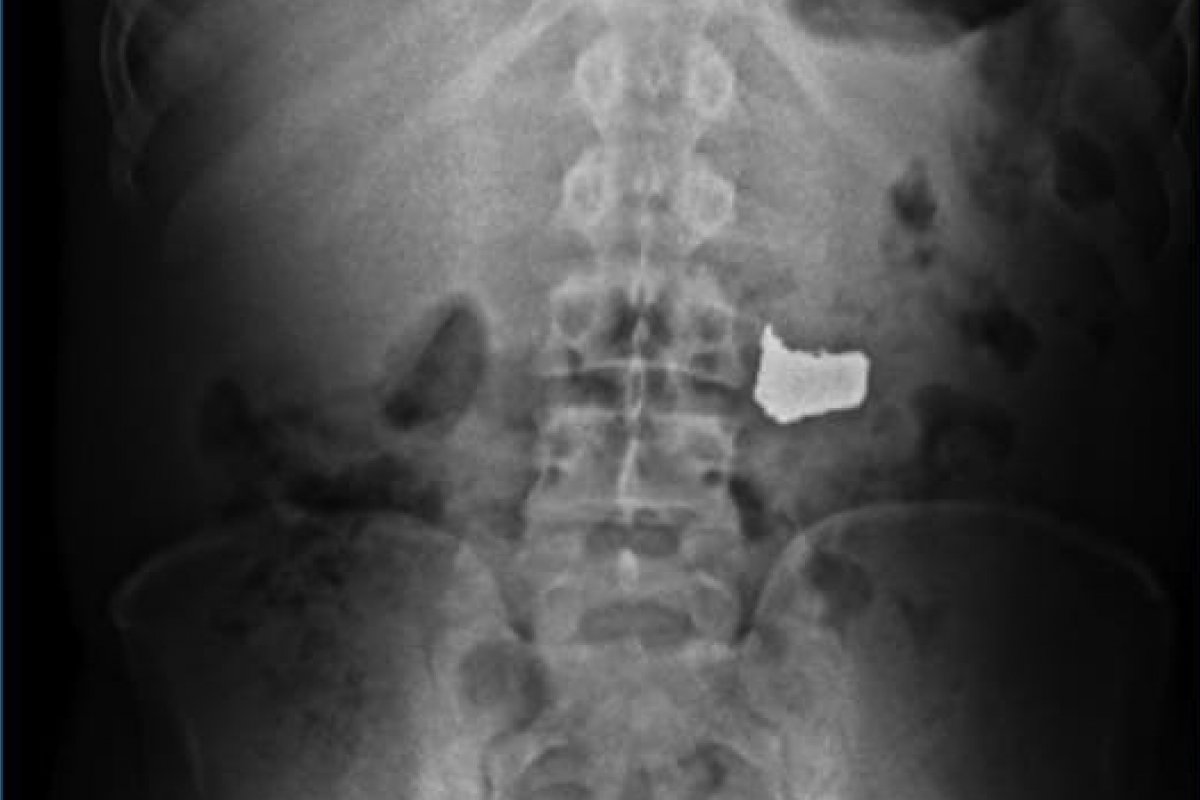

Imediatamente, as guarnições da 11ª CIPM conduziram o suspeito à UPA dos Barris, onde os médicos realizaram um exame de Raio X, confirmando a presença da corrente. Após ser liberado da unidade de saúde, o criminoso foi encaminhado à Central de Flagrantes.